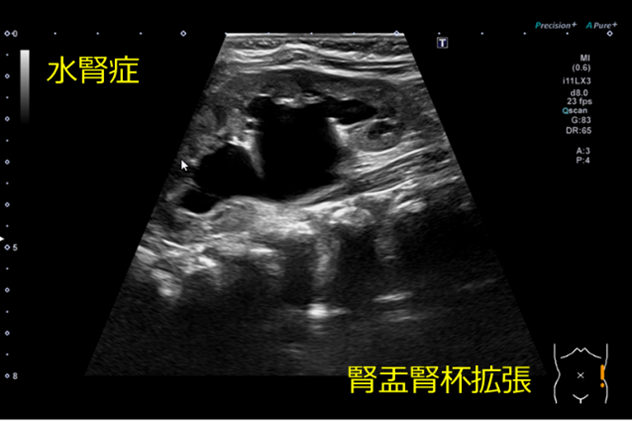

水腎症とは

腎盂、腎杯が拡張している状態を示します。

尿路障害により腎盂・腎杯に尿がうっ滞することで生じます。